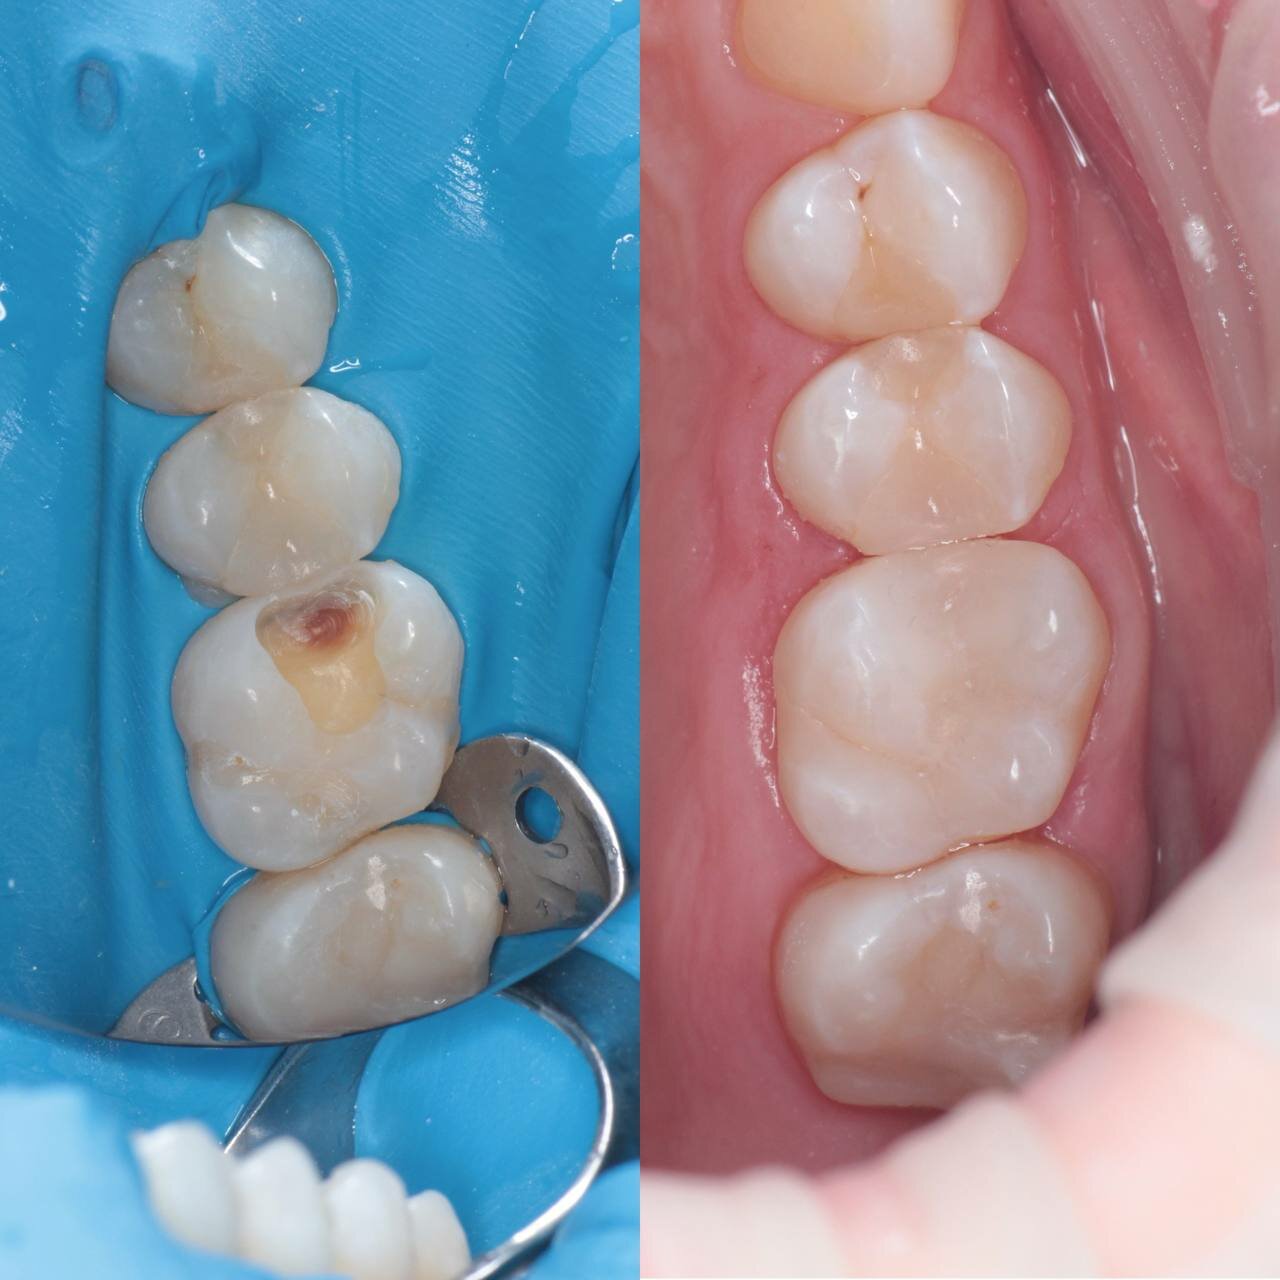

- Качественное лечение зубов.

- Долговечные и эстетичные результаты (импланты, протезы).

- Быстрое и безболезненное пломбирование.